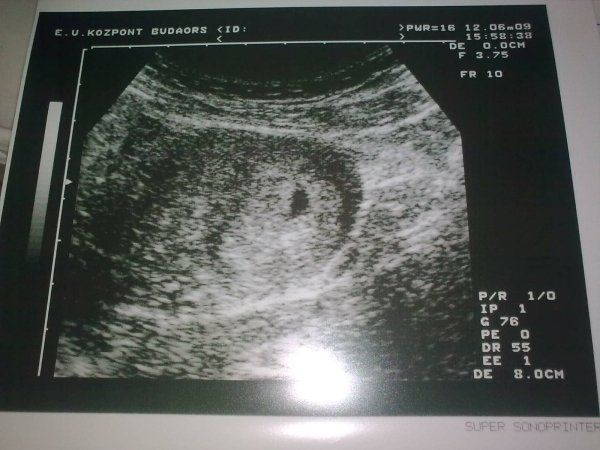

Barbi várjuk,hogy mit mondott a doki!